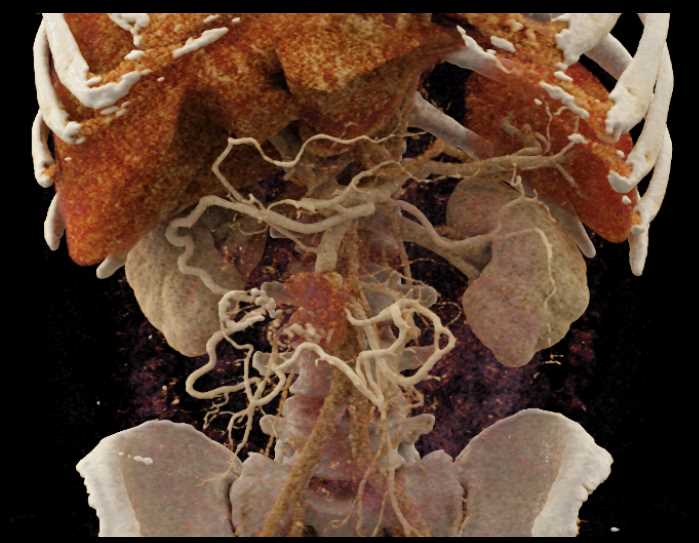

Carcinoid Tumor with Desmoplastic Reaction